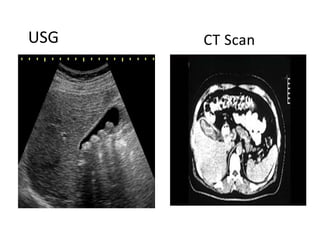

• Ultrasound

• Computerized tomography (CT) scan

• May show gallstones or complications, such as infection and rupture

USG CT Scan